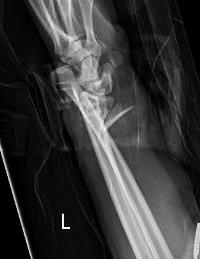

Operative management

Indication

DRUJ instability after distal radius ORIF with ulna styloid fracture

Techniques

Options

Styloid screw

Tension band wire

Ulna hook plate